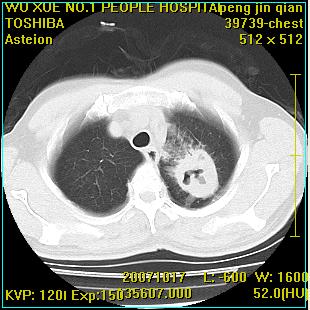

标题: CT10148:男,56岁,咳血。 [打印本页]

标题: CT10148:男,56岁,咳血。

左肺上叶尖后段较大团块影,边缘光滑,内见不规则裂隙样空洞,周围明显见细小结节及渗出,与肺门方向结构紊乱,另:左上叶尖段外侧 舌叶内侧 右上叶尖段及下叶背段均见片状致密影。考虑:继发性肺结核伴空洞形成!

左上肺厚壁空洞影、两肺多发小片样不规则高密度灶。基本上能排除转移瘤。考虑肺结核伴空洞形成。

右肺下叶背段/左上肺/左下肺结核伴空洞形成

结核 空洞伴两肺播散

浸润型肺结核伴左上肺空洞形成,两肺播散灶